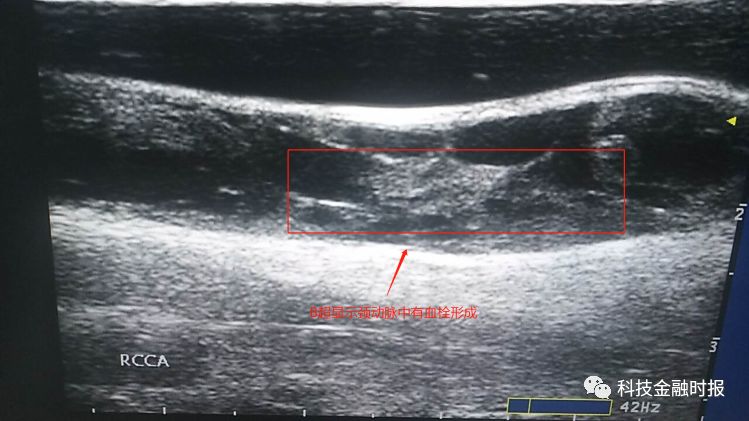

超声检查时,超声科李锋之主任凭借丰富的临床经验判断,这位患者的情况有些异样。细心的李锋之主任发现,刘女士的颈总动脉明显增粗,里面竟有血栓形成!